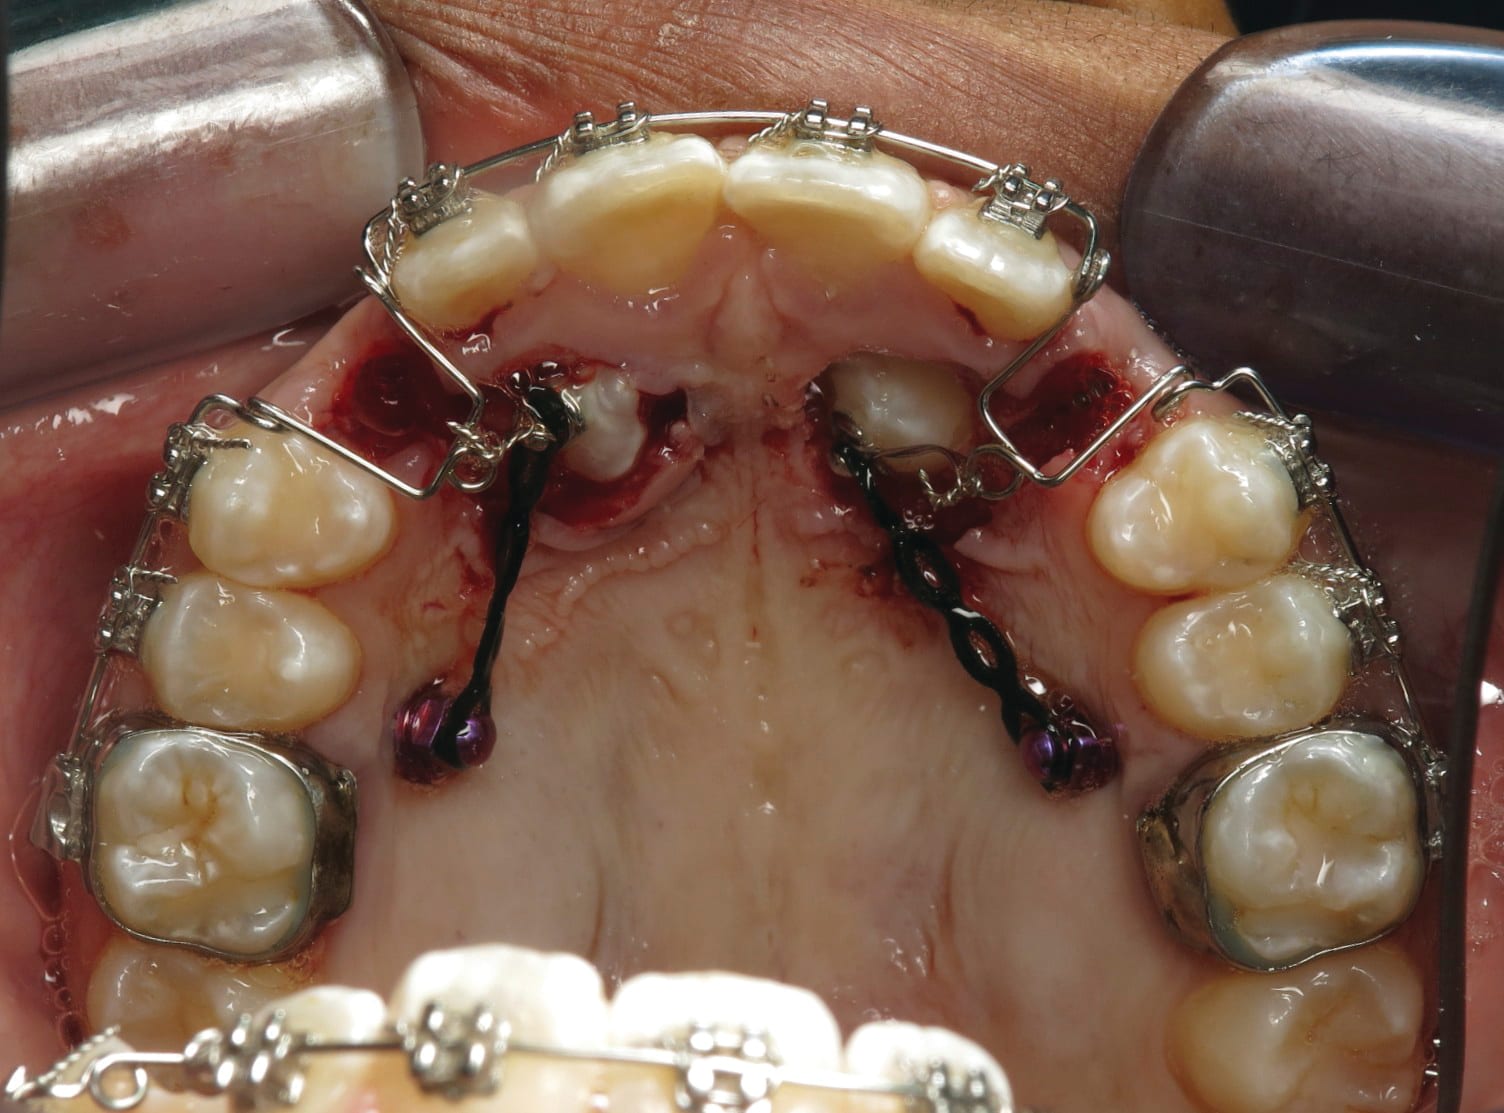

4. Any patient that will have a temporary skeletal anchorage device placed. Most clinicians that have become proficient and confident with the placement and use of TSADs place them on approximately 23% of the case treatment planned in their practices. When evaluating the placement site in all three planes of space, the clinician can become very exact with locating structures that should be avoided. More TSADs are being placed in the infazygomatic area. A 3D image is the best way to locate the optimal area of placement for stability in this area. See Figure 13 and note the thickness of the bone in the infrazygomatic crest. Compare the thickness of the bone in Figure 14. The bone in this figure demonstrates bone that is too thin for placement of the TSADs. More TSADs are being placed in to palatal approach. TSADs placed in the premaxilla are an area of placement that is vitally important to visualize the anatomy in this area. One should consider the thickness of bone in this area to avoid the tips of the TSADS from penetrating the nasal cavity and to avoid the roots of the teeth in this area. See Figure 15 through Figure 17. When skillfully placed in adequate bone, the use of TSADS certainly allows orthodontist to treat their patients more consistently and predictably. The use of 3D imaging aids the clinician in the placement and use of the TSADs.